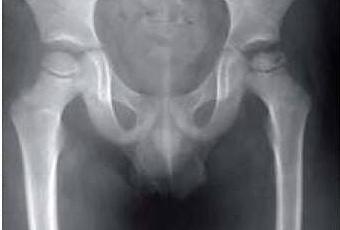

Una madre acude a su consulta con su hijo de 6 años muy preocupada porque éste presenta, estando previamente bien, cojera desde hace 5 días junto con dolor en la cadera izquierda. El paciente mide 1,20 m y pesa 59 kg. Las constantes del paciente son: temperatura 37,6 ºC, PA 121/86, FC 67 latidos por minuto. La movilidad tanto activa como pasiva de cadera es dolorosa, en especial a las rotaciones. Usted le solicita una radiografía de pelvis anteroposterior, resultado de la cual se muestra en la imagen adjunta.

¿Cuál es su diagnóstico de presunción?

a) Enfermedad de Perthes.

b) Sinovitis transitoria de cadera.

c) Artritis séptica.

d) Displasia de cadera en desarrollo.

e) Epifisiolisis femoral proximal.